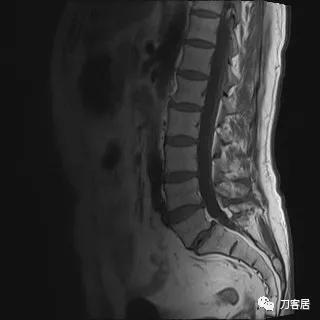

入院后予以腰椎CT及MRI检查,未见明显之椎间盘突出及椎管狭窄。

图12. 20210626术前腰椎MRIT2相2

图13. 20210626术前腰椎MRIT1相1